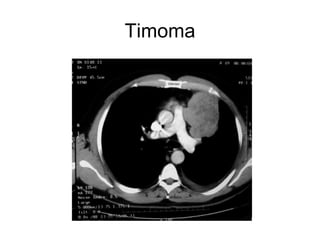

Timoma

Lesiones Mediastinales Lesiones sólidas. Bocio retroesternal Timoma (hiperplasia tímica) Tumores germinales (teratomas, seminomas o no seminomatosos). Linfoma, adenomegalias Bocio retrotraqueal. Tumores neurogénicos. Patología esofágica.